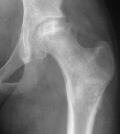

Children

in mid-childhood with sickle cell disease develop avascular necrosis

of the femoral head which responds similar to Perthes disease

of the hip.